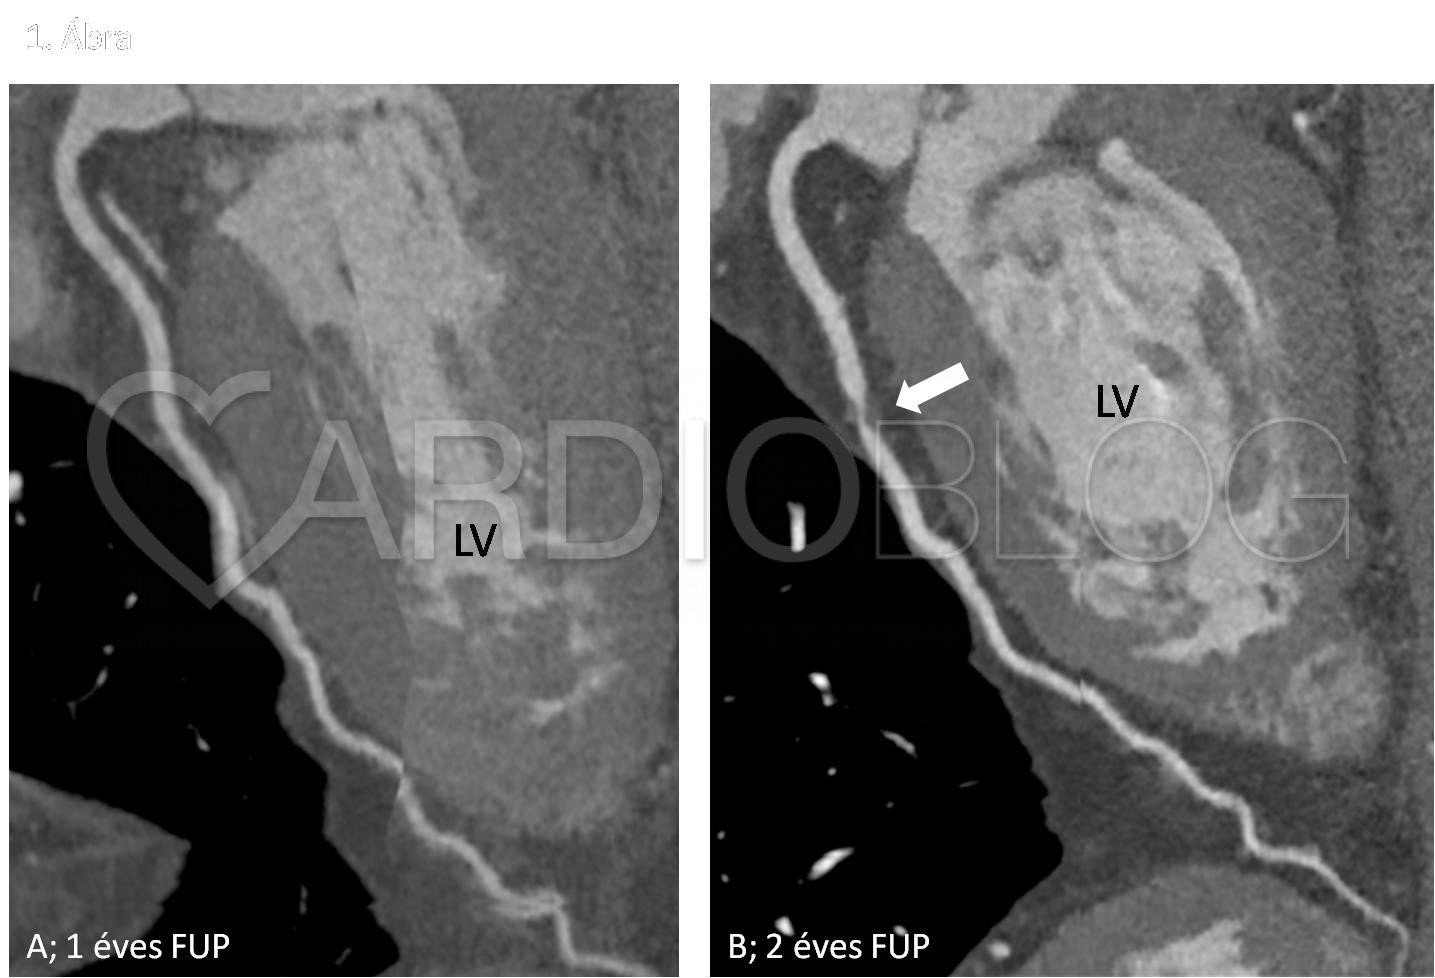

<h6>Szívtranszplantációt követő kontroll coronaria CTA vizsgálat – LAD-ról készült kanyarodó multiplanáris rekonstrukció.</h6>

<h6>A – 1 éves után követés során stenosistól mentes coronaria rendszer igazolódott<br />

B – 2 éves után követés során a LAD középső szegmentumán súlyos fokú szűkületet okozó coronaria betegség igazolható<br />

(LV – left vetricle, FUP – follow-up)</h6>